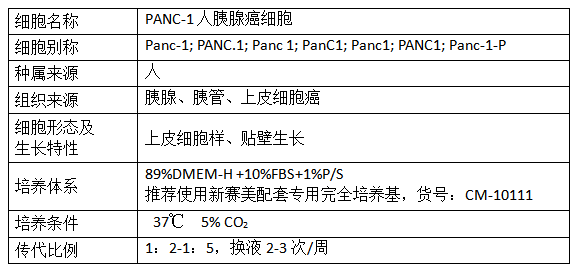

细胞产品

产品信息: